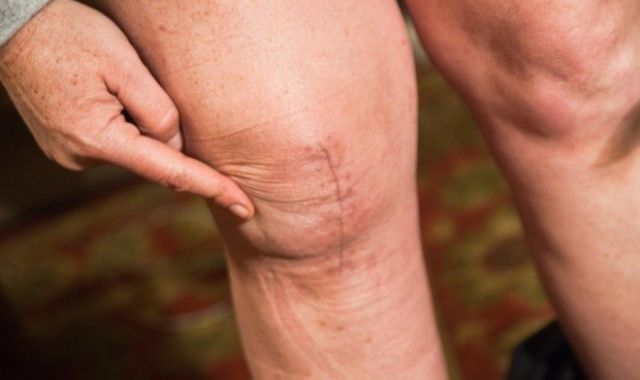

What Can Go Wrong with Knee Replacement????

Most knee joint operations are problem-free but about 1 person in every 20 may have...

5 Steps to Finding the Perfect Life after Knee Replacement

Total knee replacement has a very high success rate in relieving pain and bearing upon the...